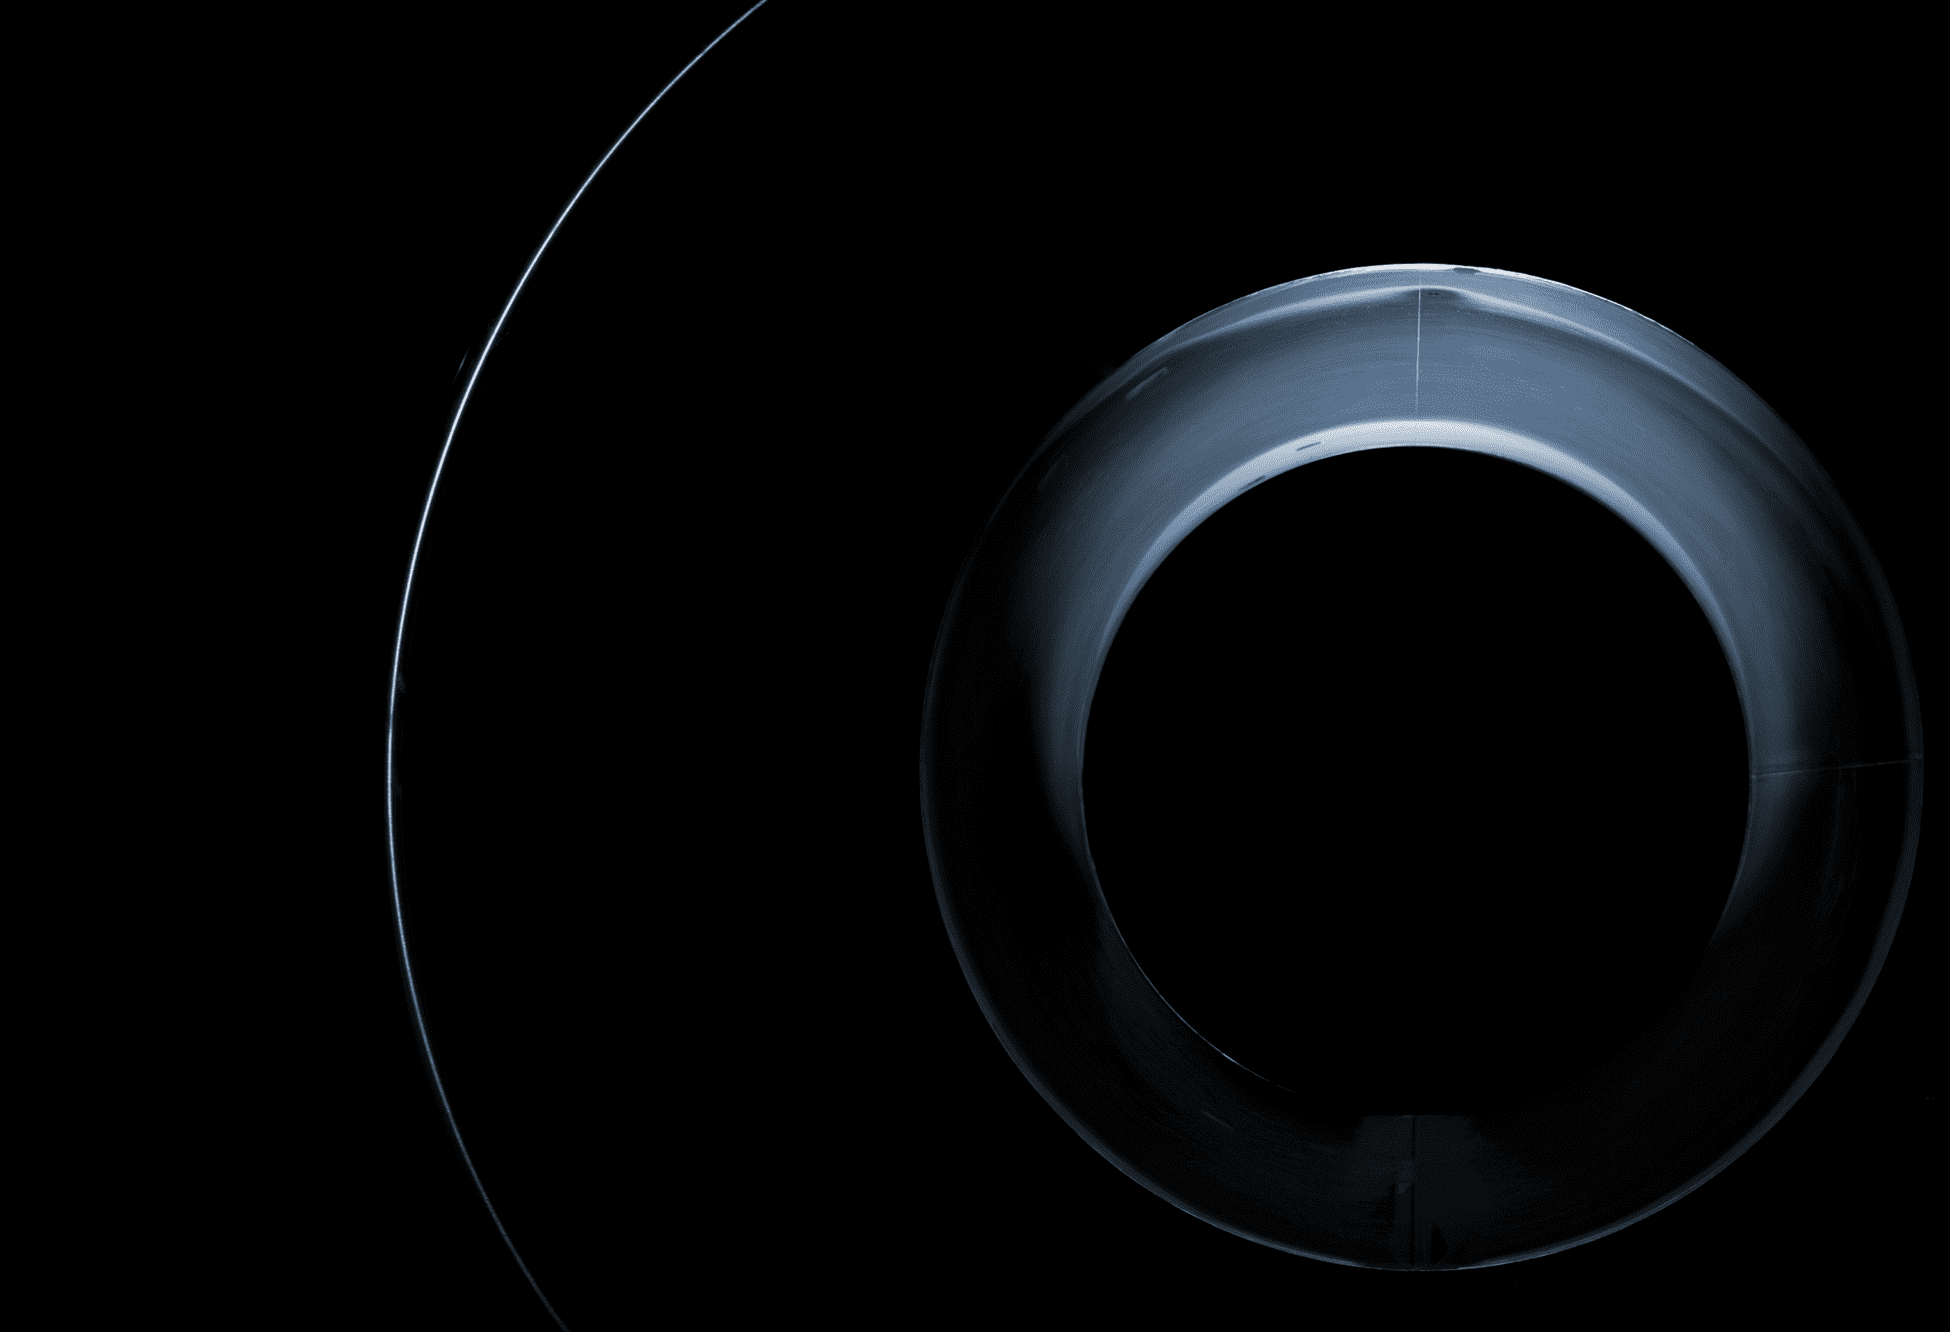

作为磁共振的「心脏」,磁体可谓「一招定乾坤」——为磁共振提供成像所必备的磁场条件,磁场越高图像分辨率越清晰。然而,高场磁体却是国内制造业难以攻克的险关。放眼全球,拥有3.0 T医用磁体制造「秘笈」的厂商也屈指可数。